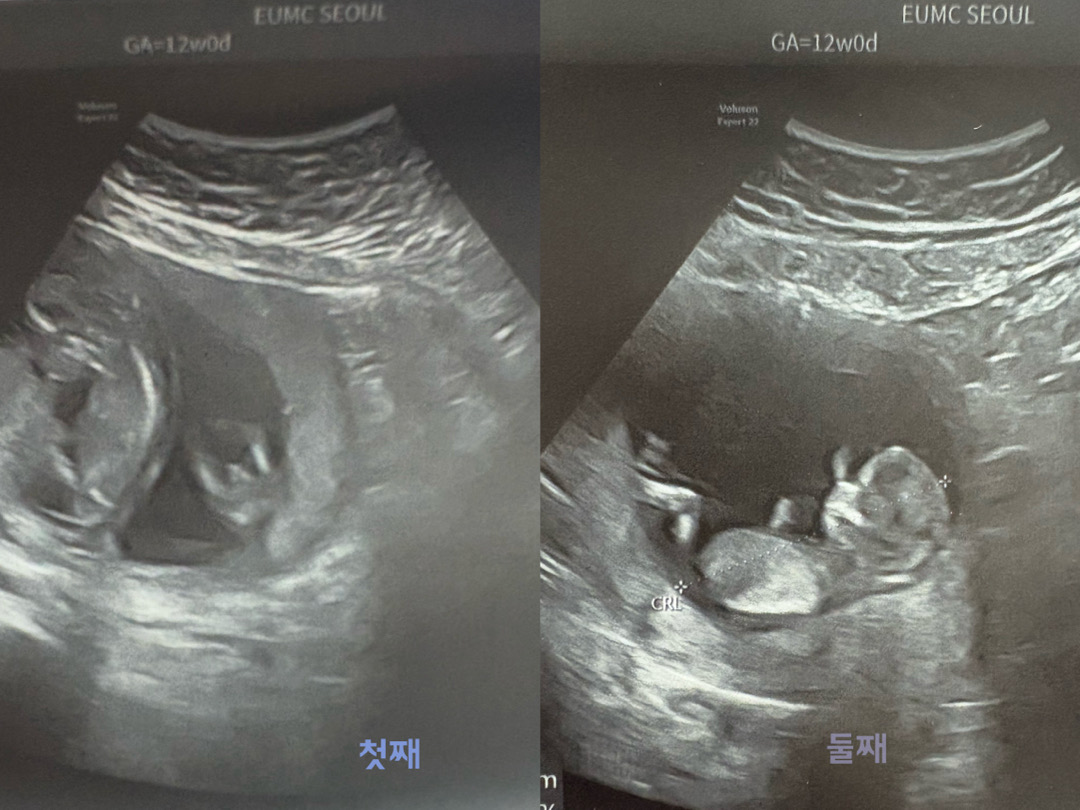

12주0일 쌍둥이 춈파에요! 첫째는 빼박 남아같죠..? 둘째는 아무리봐도 모르겠는데 여아같기도 하고.. 좀 봐주세용ㅠㅠ🙏